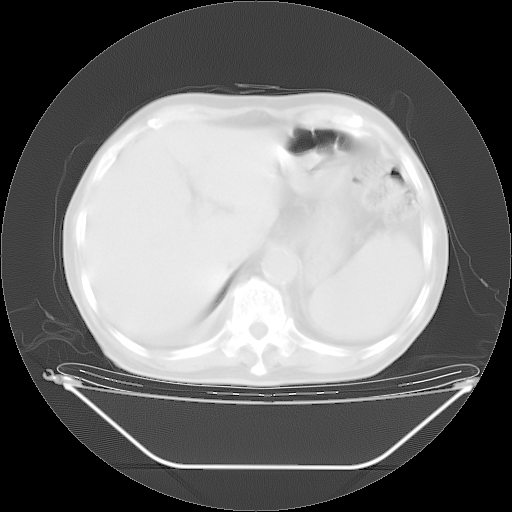

今天复查肺部CT,发现双肺广泛磨玻璃样改变。所以我把3月19日和5月9日相隔50天的肺部CT上传。请大家会诊。

5月9日肺部CT(在4月27日齐鲁医院肺部CT描述部分肺组织磨玻璃样改变,12天后肺组织广泛磨玻璃样改变)

2009年5月9日肺部CT